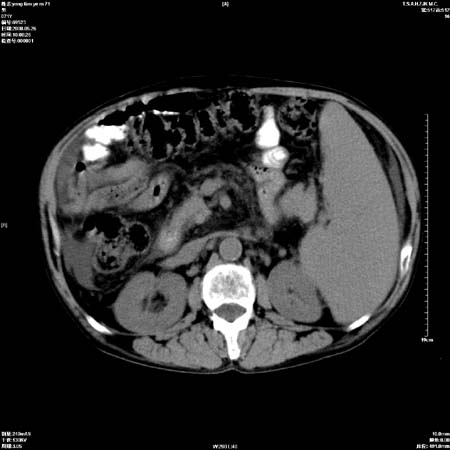

以下是引用医影拾贝在2008-6-5 22:48:00的发言:[br]肝硬化、门脉高压、胃底食管静脉曲张、低蛋白血症(胆囊壁水肿、增厚)、腹水[br]脾功能亢进、脾大、脾、左肾囊肿[br]肝囊性占位、不除外肝脓肿可能[br]建议增强以除外肝右叶肝ca可能

以下是引用chenglinhunan在2008-6-5 22:53:00的发言:[br]1. 肝硬化腹水,脾肿大。[br]2. 肝右后叶占位,肝癌。[br]3。建议ct增强扫描。

以下是引用xulianj在2008-6-5 21:40:00的发言:[br]支持肝硬化腹水;建议增强。肝、脾、肾囊肿待排。

以下是引用zjzjr在2008-6-6 12:34:00的发言:[br]1. 肝硬化腹水,脾肿大。[br]2. 肝右后叶占位,肝癌。[br]3。建议ct增强扫描。[br]4肝脾囊肿.